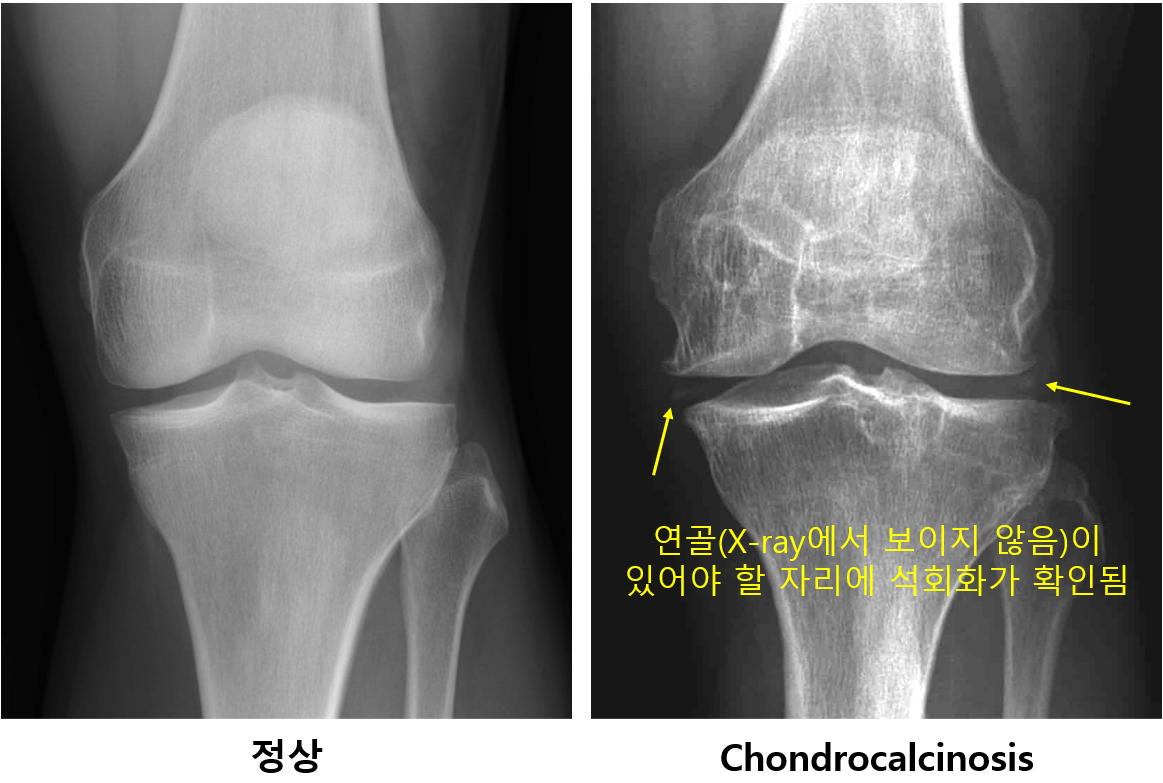

(2) Plain X-ray, US: Chondrocalcinosis - 연골의 선형, 혹은 점형의 병변이 확인됨 (결정 침착 부분)